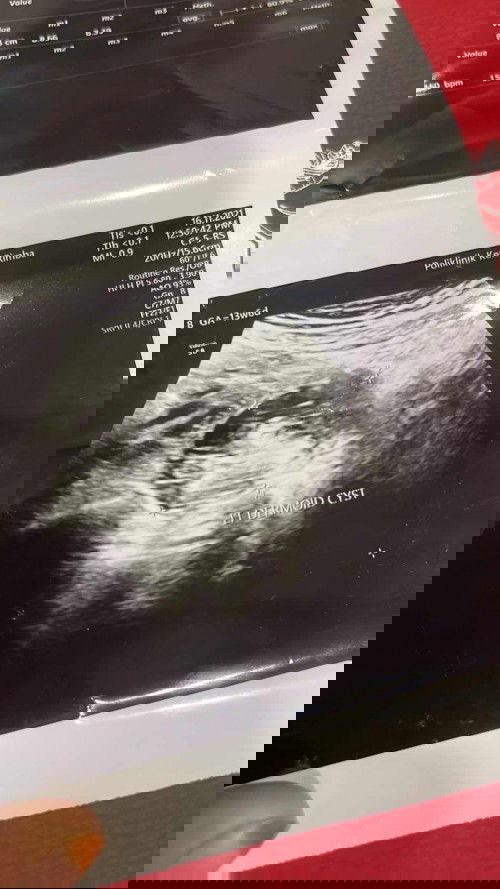

DERMOID Csyt !

Hi semua . Saya pregnant 14w skrg. Hri tu scan ade cyst dermoid . Csyt yg dalam ade rambut dan gigi. Klinik kelua kan surat utk pegi hspital. Bt mase ni sy belum pegi lg . Dan sering mrnangis . Takut . Ade ke yg sama nasib mcm sy. Dan apa solusi nya 🥲🥲